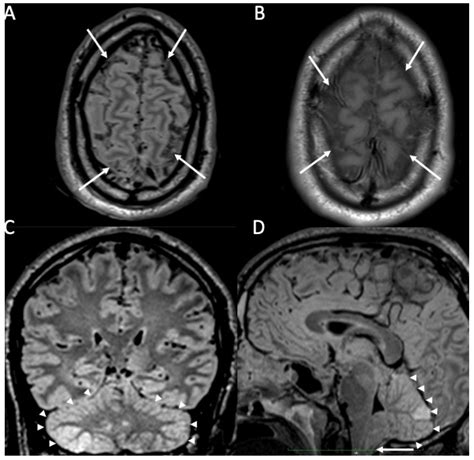

Diagnosing encephalitis involves a combination of clinical evaluation, laboratory tests, and imaging studies. The diagnostic process typically includes:

• Imaging Studies: Magnetic resonance imaging (MRI) and computed tomography (CT) scans to visualize brain inflammation and rule out other conditions.

Diagnosing meningitis involves a combination of clinical evaluation, laboratory tests, and imaging studies. The diagnostic process typically includes:

• Imaging Studies: Magnetic resonance imaging (MRI) and computed tomography (CT) scans to visualize inflammation and rule out other conditions.